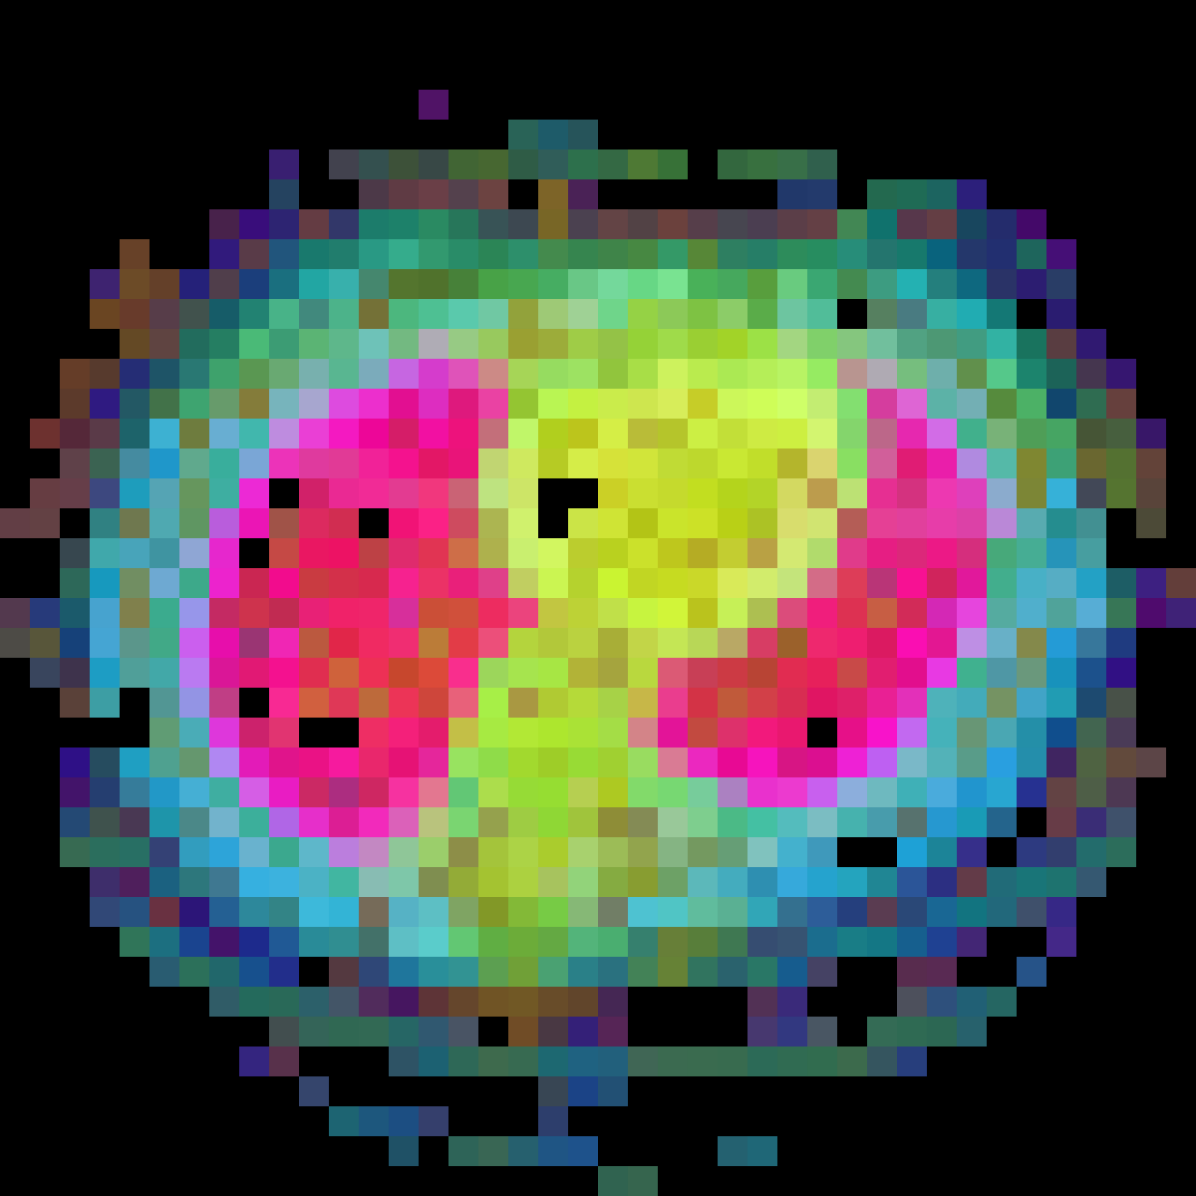

In this section we will show qualitative results of DINOv2 features using principal component analysis (PCA) performed on DINOv2 patch features on X-ray, CT, and MRI scans, following the method delineated in [8]. We will also provide organ segmentation results of linear compared U-Net decoders.

PCA visualization. Figure 2 shows the first three PCA components. The PCA is computed between patches of images that are in the same column, and the first 3 components are shown for X-ray, CT, and MRI scans. Thresholding is used on the first PCA component to remove the background. Just like in natural images [8], the colors of the three PCA components correspond well with the same parts of images in the same category. This is an easier task however, compared to natural images, because there is less variability between examinations on medical images compared to natural images.